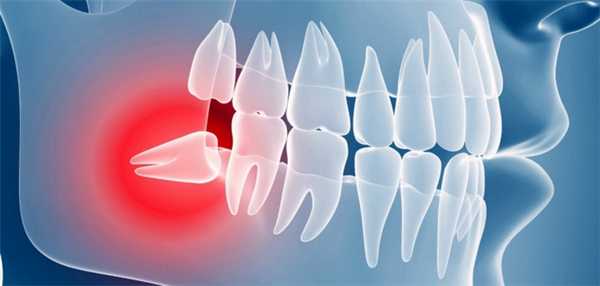

Ретинированным называется зуб, находящийся в толще костной ткани челюсти, полностью сформированный, но не прорезавший десну в предполагаемые сроки.

Ретинированный зуб - затруднение полноценного прорезывания зуба, находящегося в челюстной кости или прикрытого десной. Ретенция - часто встречающаяся аномалия прорезывания зубов. По статистике, наиболее часто ретинированными оказываются нижние и верхние третьи моляры (зубы мудрости), клыки верхней челюсти и вторые премоляры нижней челюсти. При этом непрорезавшиеся «восьмерки» встречаются у 35-45% наблюдений. Лечение ретинированных зубов представляет собой сложную и актуальную проблему современной хирургической стоматологии и ортодонтии.

В зависимости от степени выделяют полную и частичную ретенцию и соответственно ретинированный и полуретинированный зуб. Ретинированный зуб полностью покрыт десной или костной тканью, не виден в полости рта и не доступен для пальпации. Коронковая часть полуретинированного зуба частично прорезана, однако ее большая часть остается прикрытой тканями десны. С учетом глубины залегания различают ретинированные зубы с тканевым погружением (зуб расположен в тканях десны) и костным погружением (зуб расположен в челюстной кости).

Положение корня и коронки ретинированного зуба в десне или кости может быть:

- вертикальным - ось зуба имеет нормальное положение, совпадающее с вертикальной линией;

- горизонтальным - ось зуба образует с вертикалью прямой угол; при этом положение зуба может быть поперечным, сагиттальным или косым;

- угловым (ангулярным) - ось зуба образует с вертикалью угол, меньше 90°. В зависимости от наклона различают медиально-угловое (с наклоном вперед), дистально-угловое (с наклоном назад), язычно-угловое (с наклоном вовнутрь, в сторону языка) и щечно-угловое (с наклоном кнаружи, в сторону щеки) положение.